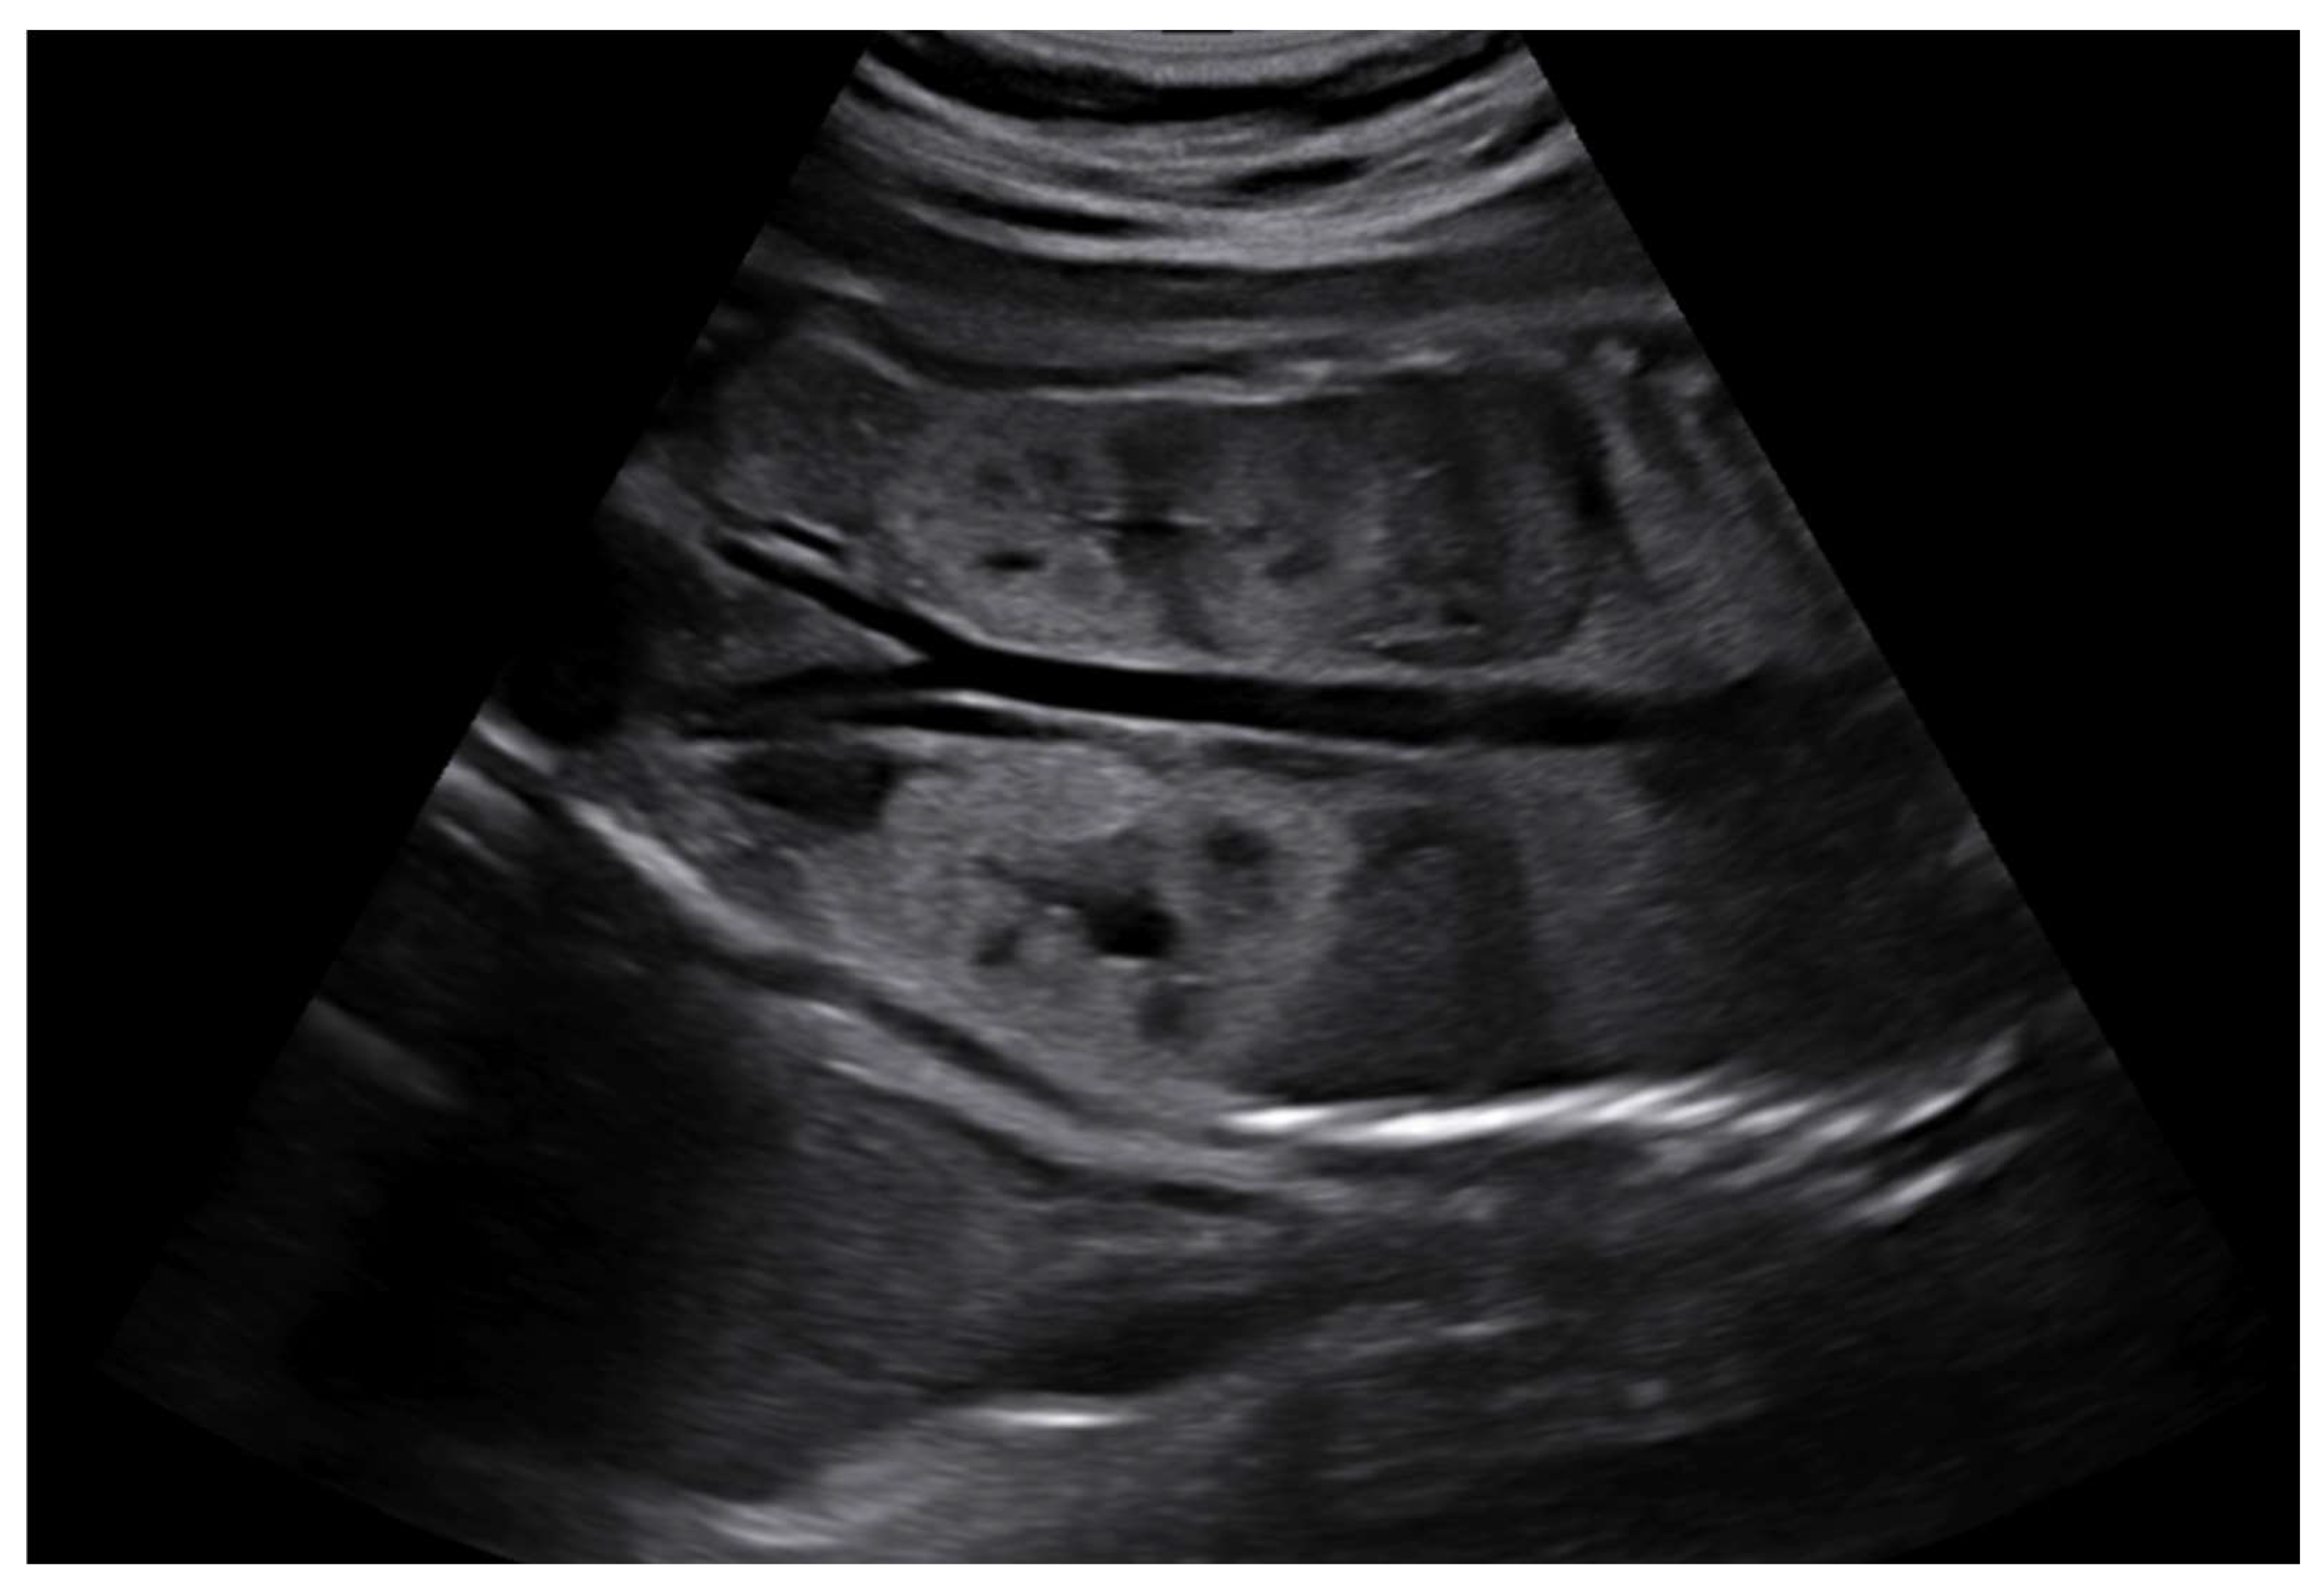

- Brun, M.; Maugey-Laulom, B.; Eurin, D.; Didier, F.; Avni, E.F. Prenatal sonographic patterns in autosomal dominant polycystic kidney disease: A multicenter study. Ultrasound Obstet. Gynecol. 2004, 24, 55–61. [Google Scholar] [CrossRef]

- Garel, J.; Lefebvre, M.; Cassart, M.; Della Valle, V.; Guilbaud, L.; Jouannic, J.M.; Ducou le Pointe, H.; Blondiaux, E.; Garel, C. Prenatal ultrasonography of autosomal dominant polycystic kidney disease mimicking recessive type: Case series. Pediatr. Radiol. 2019, 49, 906–912. [Google Scholar] [CrossRef]

- Gupta, A.; Aneja, A.; Bahl, N.; Arora, R.; Nadir, L.; Saini, P. Corticomedullary differentiation in fetal kidneys: A necessary evil? J. Fetal Med. 2024, 11, 139–144. [Google Scholar] [CrossRef]

- Buffin-Meyer, B.; Klein, J.; Aziza, J.; Fernandez, M.; Feuillet, G.; Seye, M.; Buléon, M.; Fédou, C.; Camus, M.; Burlet-Schiltz, O.; et al. Improved prenatal assessment of kidney disease using multiple ultrasound features. Nephrol. Dial. Transplant. 2025, 40, 341–351. [Google Scholar] [CrossRef]

| CMD | |

| Increased CMD | 15 (75.0%) |

| Reverse CMD | 1 (5.0%) |

| Loss of CMD | 2 (10.0%) |